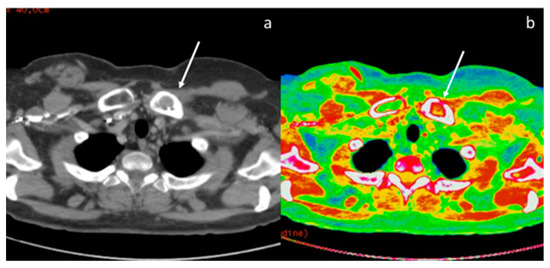

- Lennartz, S.; Le Blanc, M.; Zopfs, D.; Hokamp, N.G.; Abdullayev, N.; Laukamp, K.R.; Haneder, S.; Borggrefe, J.; Maintz, D.; Persigehl, T. Dual-Energy CT-derived Iodine Maps: Use in Assessing Pleural Carcinomatosis. Radiology 2019, 290, 796–804. [Google Scholar] [CrossRef]

- Zhang, X.; Duan, H.; Yu, Y.; Ma, C.; Ren, Z.; Lei, Y.; He, T.; Zhang, M. Differential diagnosis between benign and malignant pleural effusion with dual-energy spectral CT. PLoS ONE 2018, 13, e0193714. [Google Scholar] [CrossRef] [PubMed]